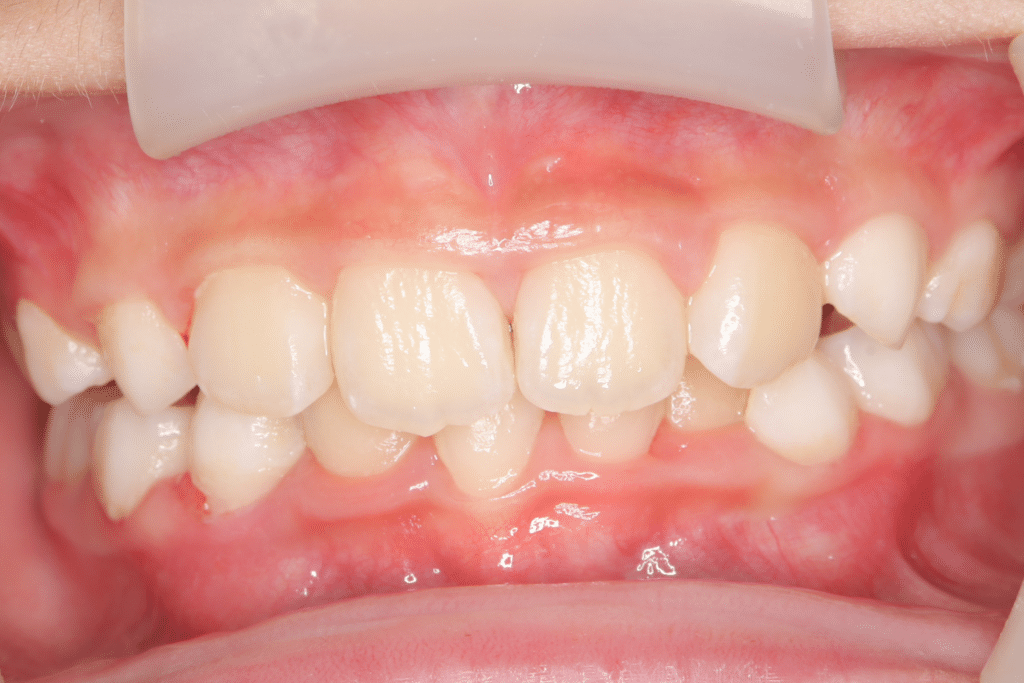

過蓋咬合

(9歳10ヶ月)

開始後8ヶ月

過蓋咬合(かがいこうごう)を改善

症状:過蓋咬合(かがいこうごう)

期間:8か月

開始年齢:(9歳2ヶ月)~

終了年齢:(9歳10ヶ月)(過蓋咬合は改善したが、叢生がまだ残っているため、今後は叢生の治療を開始予定)